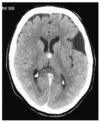

There is a mass in the left hemisphere (A) surrounded by an extensive area of low density (B) which represents oedema. There is midline shift (C) and compartmental hydrocephalus (demonstrated by the enlarged lateral ventricles on the right (D) due to compression of the ventricular system at the foramen of Monro. There is herniation of the uncus of the left temporal lobe seen on the lower slice (E).

The mass exhibits ring enhancement. The differential diagnosis is between a highgrade glioma, an abscess, and metastasis. In the absence of raised infective markers, a tumour is more likely